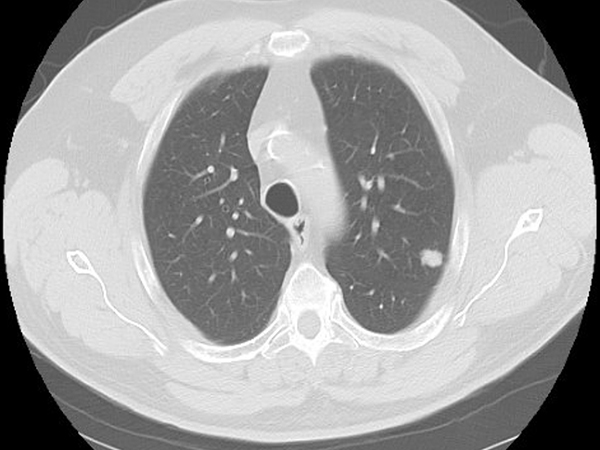

Clinical History: A 68-year-old man was found to have a suspicious left upper lobe nodule on a cancer screening chest CT (Figure 1). He was a former smoker. The patient underwent a VATS left upper lobe segmentectomy. Pathologic review demonstrated two distinct morphologies within the tumor (Figure 2). The periphery of the tumor was an adenocarcinoma with micropapillary and acinar growth patterns (Figure 3) whereas the center demonstrated a solid growth pattern composed of cords and nests of cells with moderate cytoplasm, pleomorphic nuclei with speckled chromatin and prominent nucleoli, areas of necrosis, and mitotic rate of up to 11 mitoses per 10 HPF (Figure 4). Immunohistochemical characterization of the tumor area corresponding to Figure 2 by TTF-1 (Figure 5), synaptophysin (Figure 6), and napsin A (Figure 7) is shown.